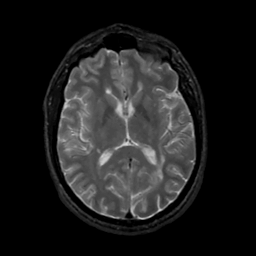

MR Study #1, February 10, 1991 -- Slice #27